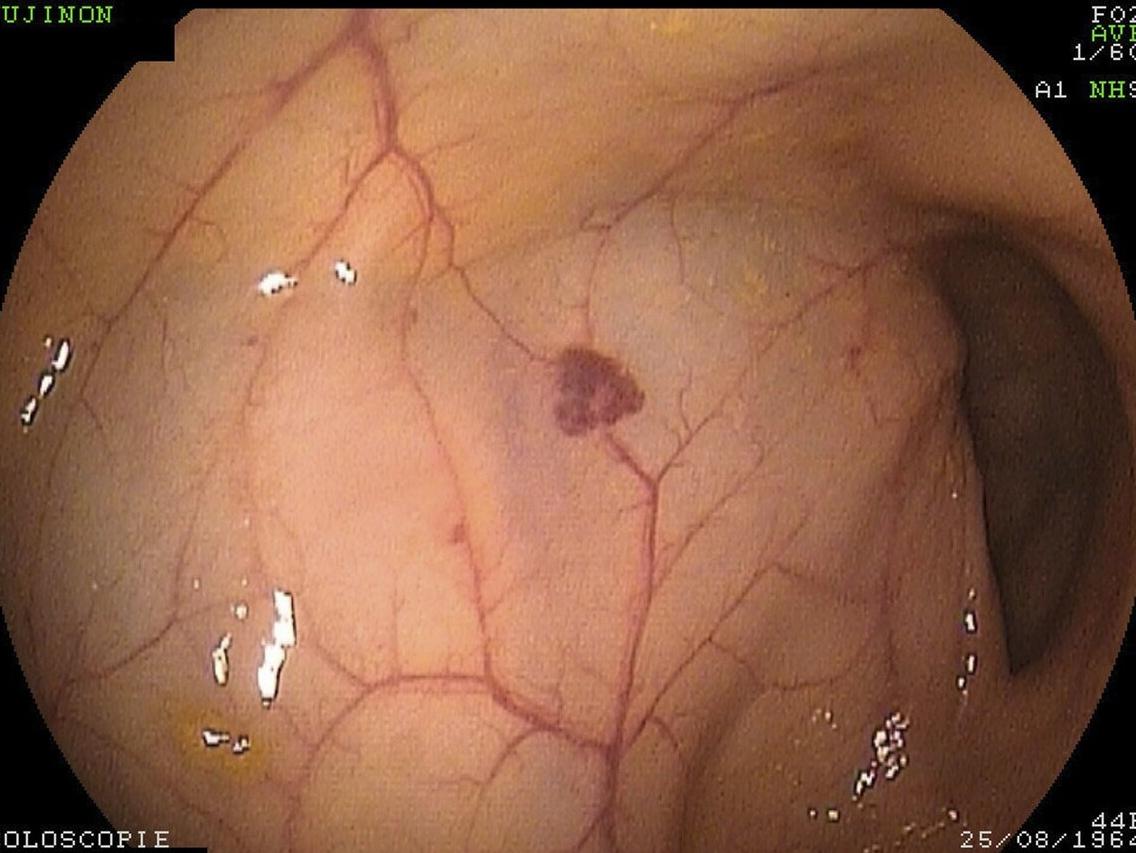

虽然脑动脉瘤并不是脑瘤,但并不意味着它就很安全!脑动脉瘤被称为脑袋中的“定时*弹炸**”,它最主要的危害就是破裂出血。

如果患者血管内的压力突然增大,例如情绪激动、用力搬重物、剧烈运动、甚至是排便时过于用力,都会造成动脉瘤的破裂。

一旦发生破裂,大概30%-40%的患者会当场死亡, 即使能够及时抢救并且动了手术,仍然会有不少人会严重残疾。所以,建议大家不要轻视这个疾病!